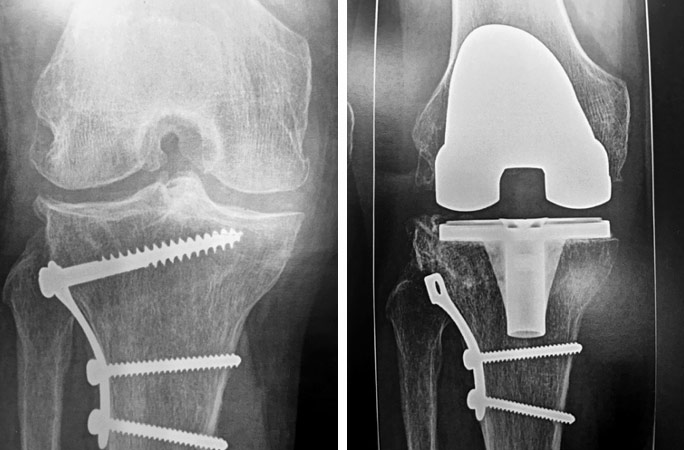

Douleur, raideur, boiterie. Usure prothétique avec métallose. Evolution arthrosique associée avec pincement fémoro-tibial interne.

On propose une reprise chirurgicale : ablation du bouclier métallique trochléen, mise en place d’une prothèse totale du genou NexGen.

Homme 60 ans, opéré par prothèse rotulienne et prothèse uni-compartimentale interne. Toujours douloureux.

Pas d’infection.

Changement pour mettre en place une prothèse totale du genou. Aucune douleur résiduelle.